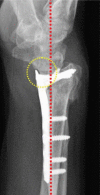

Greater understanding of specific fracture patterns following distal radius fractures has arisen with the advent of volar plating. The volar marginal fragment (VMF) is a small peripheral piece of bone which is critical to carpal stability. Failure to achieve good fixation of the VMF can result in volar subluxation of the carpus and distal radioulnar joint instability. Due to its small, distal nature, this fragment can be easily missed and difficult to fix. Loss of reduction of the VMF following operative fixation presents specific challenges and surgical considerations dictated by patient characteristics and timing. Our goal of this review is to present a classification system for these failed VMFs which can help guide surgical treatment as well as expected outcomes.